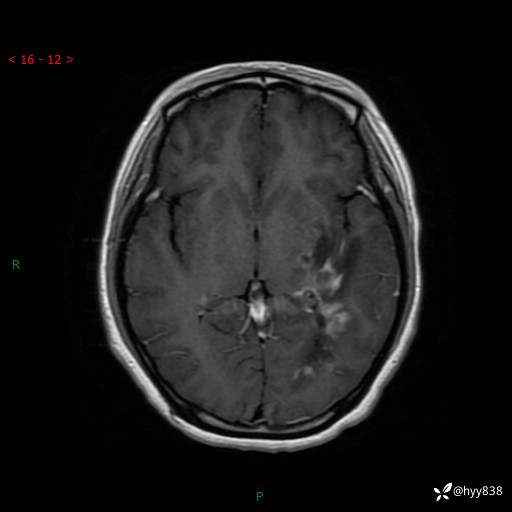

颅脑MRI平扫+增强